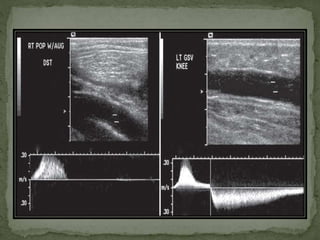

 For popliteal v exam, prone position with slight knee

flexion.

 Below knee , pop. V. lies superficial to pop art.

 At popliteal Vein – with distal venous augmentation.